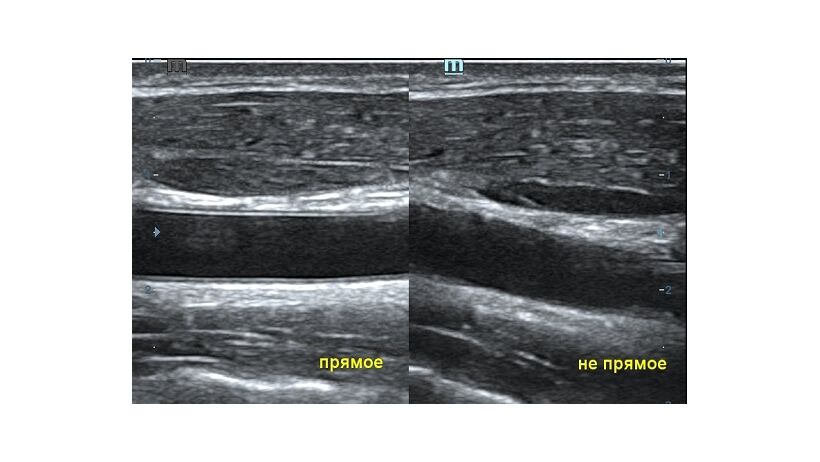

Ультразвуковая волна распространяется от пьезокристалла в направлении плоскости сканирования. Если волна отражается от поверхности исследуемой структуры под прямым углом и возвращается к пьезокристаллу напрямую, на сонограмме появляется четкая дифференцировка структуры и подчеркнутые контуры. Прямое отражение - самый важный критерий техники сканирования для измерения точных размеров органа. В случае отражения волны не под прямым углом эхогенность структуры меняется, дифференцировка на слои падает, контуры становятся нечеткими. Таким образом косой срез дает огромную погрешность измерения и затрудняет описание эхоструктуры объекта.

Как достичь прямого отражения Достаточно расположить объект на экране горизонтально, с помощью наклона датчика, чтобы волна отражалась от поверхности под прямым углом. При любом типе исследования любого органа или системы прямое отражение – залог достоверных результатов.